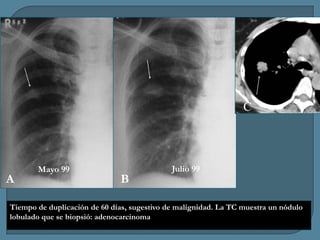

Mayo 99

B

Julio 99

Tiempo de duplicación de 60 días, sugestivo de malignidad. La TC muestra un nódulo

lobulado que se biopsió: adenocarcinoma